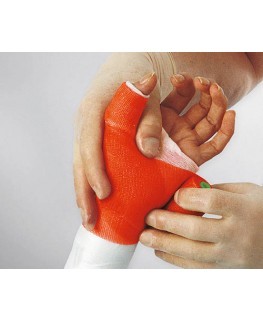

U Privatnoj ortopedskoj ordinaciji „Dr.Muharemović“ savjetujemo plasiranje Cell cast Xtra gipsa (L&R). Isti je jako lagan, tvrd čime se obezbjeđuje stabilnost ulomaka i puno lakši za nošenje od standardnog. Može se naći u raznim bojama kao npr, modro plava ili tamno zelena, te je i estetski jako zanimljiv.